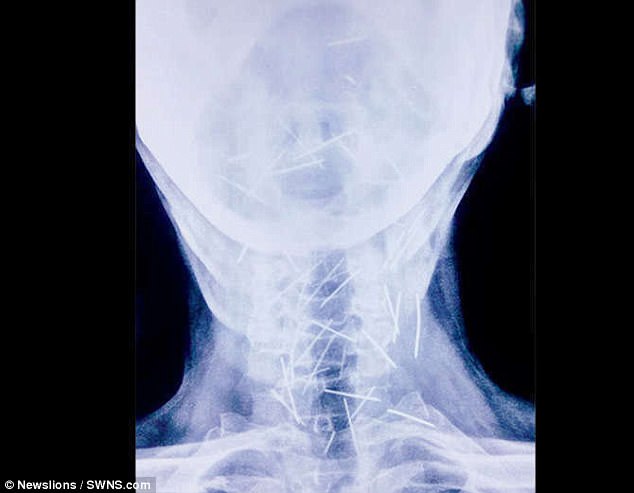

Những bức ảnh chụp x-quang về số lượng đinh khắp người ông. (Ảnh: dailymail)

Ông đã mất hơn 30kg trong quá trình tìm kiếm bệnh viện chịu tiến hành cuộc phẫu thuật lấy đinh ra khỏi cơ thể ông. Sau nỗ lực tìm kiếm, ông Badrilal đã tìm thấy các bác sĩ ở Viện Khoa học Y tế châu Á (AIMS) tại Faridabad đồng ý sẽ giúp đỡ mình lấy những cây đinh đó ra. Và đội ngũ các bác sĩ này đã tìm thấy thêm 75 cây đinh nữa. Tổng cộng, trên cơ thể người đàn ông này đã được tìm thấy 150 cây đinh - một con số gây sốc với các bác sĩ.

Người đàn ông 56 tuổi này đến từ miền Bắc Ấn Độ kiên quyết khẳng định ông không hề nhét 75 cây đinh đó vào cơ thể và không hề biết vì sao mình nó lại tồn tại trong cơ thể mình. “Khi ông ấy đến đây, tình trạng ông rất nghiêm trọng. Không thể nói chuyện, ăn uống, cơ hội sống sót rất thấp nhưng chúng tôi vẫn quyết định nhận ca bệnh đặc biệt và đầy thách thức này”, bác sĩ Parashar - Giám đốc AIMS cho biết.

Cho đến nay, sau 3 cuộc phẫu thuật, đã có 91 cây đinh được lấy ra, một số cây đã bị gỉ sét và theo các bác sĩ dự đoán, có thể nó đã tồn tại trong cơ thể ông hơn 6 tháng. Bác sĩ Lalit Mohan Parashar - người đã điều trị cho ông Badrilal - cho biết: “Để lấy những cây đinh đó ra an toàn là một thách thức lớn. Một vài cái cắm sâu vào khí quản, thực quản và cả động mạch cung cấp máu nuôi não”.